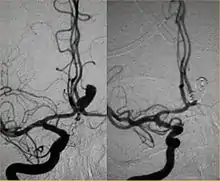

Endovascular modalities for intracranial aneurysms[2]

Between the end of the 1980s and the beginning of the '90s, INR was suddenly revolutionized after the work of two Italian physicians: Cesare Gianturco and Guido Guglielmi. The first combined a deep knowledge of diagnostic radiology with a great ability to solve technical and manual problems. He invented Gianturco's coils, which he used to make the first attempts to embolize arteries and aneurysms.[8] Gianturco also patented the first endovascular stent approved by the American FDA;[8] a device with a great legacy. In the second half of the 1980s, Sadek Hilal was the first in Columbia University to use coils to treat brain aneurysms; but this technique was inaccurate and dangerous because the coils were released with little control with great risk of occluding the vessel from which the aneurysm originated (parent vessel).[9] The coil embolization was revolutionized by the work of Guido Guglielmi in UCLA, who realized that electricity could function as a controlled release mechanism for coils; in 1991 he published two works dealing with the embolization of brain aneurysms by means of detachable platinum coils[10] (Guglielmi's coils). The treatment of aneurysms was thus made more accessible and safe.

New techniques: Sole stenting and flow diversion stents

From the early 2000s, intracranial stents were used to prevent the coils inside the aneurysmal sac from protruding into the parent artery.[11][12] Flow diversion devices were later developed, with the function of reconstructing the vessel's normal anatomy without directly closing the aneurysm neck and therefore preserving side branches and preventing ischemia.[13] The sole stenting[14] procedure involves the insertion of a stent only (without any coils) into the vessel that has an aneurysm.[15]